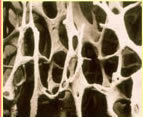

骨質疏鬆骨質疏鬆資料

骨質疏鬆2、骨質疏鬆症的藥物治療

骨質疏鬆1.雌激素:是防治絕經後骨質疏鬆症的首選藥物。(1)雌二醇1-2mg/d。(2)乙烯雌酚0.25mg/每晚。(3)複方雌激素0.625mg/d。(4)尼爾雌醇2mg/半月。(5)利維愛。